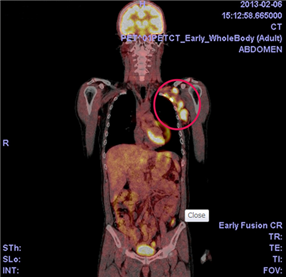

PET検査>(ポジトロン・エミッション・トモグラフィ)

ガンの発見や良性悪性の区別,転移・再発診断に使用

ブドウ糖に近い成分(FDG)検査薬を投与し

全身の細胞のうち目印である

擬餌ブドウ糖が

集まって光っているスポットから

ガン細胞を発見する

「ガンは砂糖で生きている」

「ガンは正常細胞の何十倍も砂糖を食べる」

を機械化した検査

ワールブルグ博士様さまの検査です。

PET検査によりガンの早期発見が飛躍的に進んだ